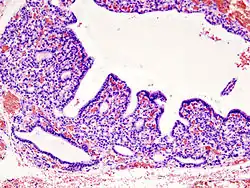

Atrophy: Decrease in organ size/tissue mass by decrease in cell size and/or in cell count.

Involution - normal atrophy, e.g. thymus in adults, uterus in the older woman.